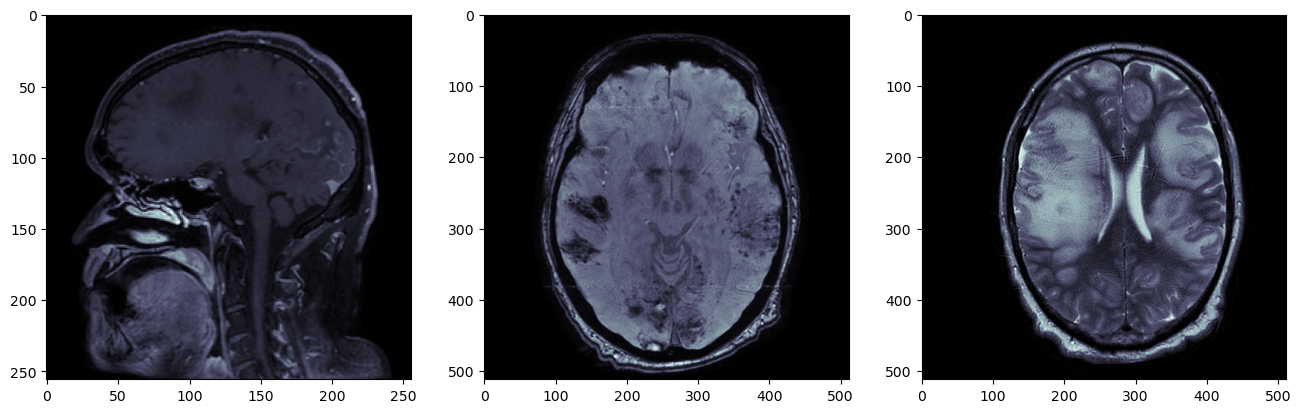

plt.imshow(t2_nib_array[:,:,t2_nib_array.shape[2]//2], cmap='gray')

t2

Это воксельный массив. Его расположение в пространстве томографа представлено в матрице аффинного преобразования:

plt.figure(figsize=(12,6))

plt.subplot(121)

plt.imshow(t1_nib_array[:,:,t1_nib_array.shape[2]//2])

plt.subplot(122)

plt.imshow(t2_nib_array[:,:,t2_nib_array.shape[2]//2])

t1t2

plt.imshow(t2_sitk_array[t2_sitk_array.shape[0]//2,:,:])

plt.imshow(t1_resampled_array[t1_resampled_array.shape[0]//2,:,:])

t2t1resampled